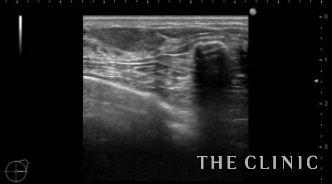

10年前に脂肪注入をされた方です。エコーでみると、右胸の下方に25㎜大のしこりがあり石灰化しています。中身はオイルと古い脂肪です。左胸上方には13㎜大のしこりがあり、中身はオイルです。右の石灰化しているしこりは、被膜が薄いためベイザーで崩していきます。左のしこりは穿刺処置となりました。

右)このカプセルをバスケットカニューレを使い、石灰化を崩しておきます。被膜がやわらかくなり折れ曲がって見えます。左)上段左側のしこりを穿刺処置したあとです。